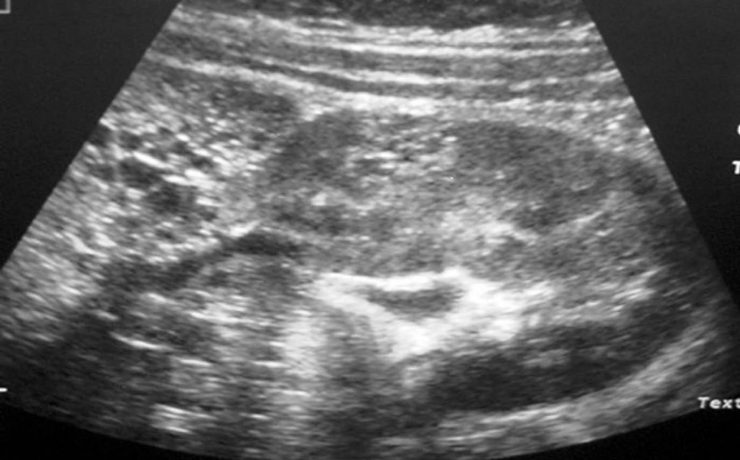

La muerte u óbito fetal se define como la ausencia de latido cardíaco, pulsación de cordón, respiración espontánea y movimientos del feto, antes de la separación completa del cuerpo de la madre. Aunque en algunos países se considera desde que el feto pesa 350 g y en otros se utiliza